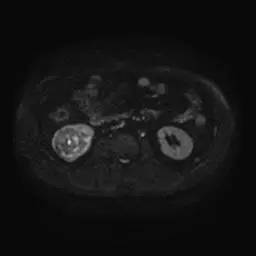

右肾中下部见类圆形约52*49*59毫米类圆形短和稍长T1、短和长T2异常信号肿块,可见假包膜,DWI呈晕环结节状稍高和稍低信号,反相位图像病变信号未见异常减低;皮质期病变未见异常强化,髓质期及延迟期持续轻度强化;病变内小部分区域未见强化。所见肝胆、胰腺、脾脏及双侧肾上腺未见异常,肝门、肾门及所见腹膜后未见异常肿大淋巴结影。

影像诊断:右肾中下部少血供肿块伴出血、坏死和囊变,考虑:恶性肿瘤,以肾癌(非透明细胞癌)可能性最大,不能完全除外表现不典型的血管平滑肌脂肪瘤。